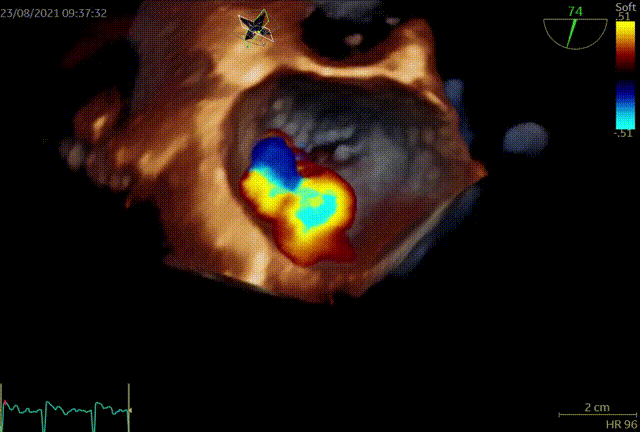

手术于全麻下进行,手术采用经典股静脉房间隔途径,房间隔穿刺后置入24F导引导管及二尖瓣夹输送系统,在TEE引导下准确植入一枚二尖瓣夹,瓣膜夹位置稳定,植入后返流基本消失,二尖瓣跨瓣平均压力阶差4mmHg,双孔化形成,遂移除器械输送系统。患者术后恢复良好,瓣膜夹位置稳定,拟于近期出院。此次手术得到了医院领导、心胸外科、麻醉科、体外循环组、重症医学科及医务科等科室的大力支持。

术后TEE提示,二尖瓣夹植入后返流基本消失,双孔化形成